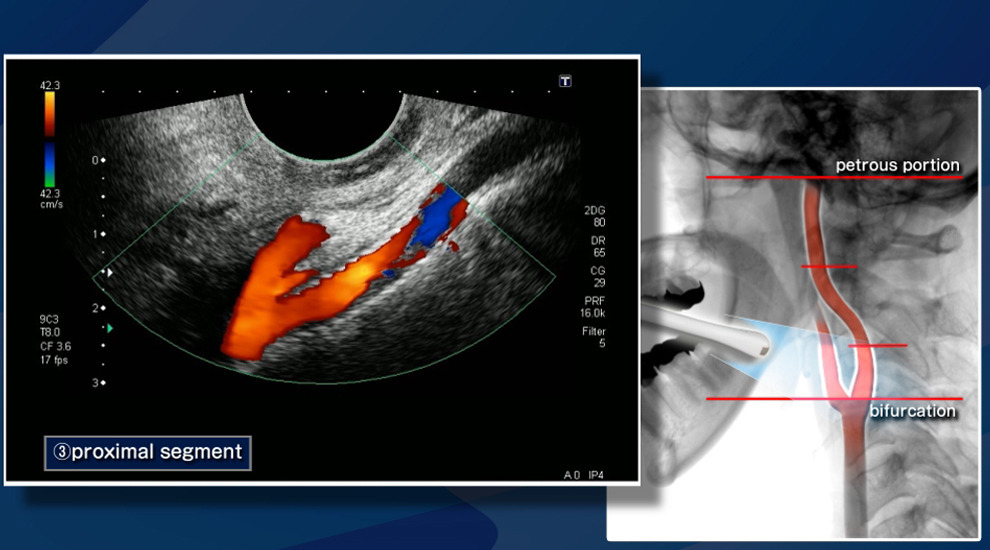

- 젤을 바른 후 초음파 탐촉자를 경동맥 위에 대고 영상 관찰

- 혈류 속도 측정과 플라크 유무 확인

- 플라크 위치와 크기

- 협착률(혈관이 얼마나 좁아졌는지 퍼센트로 표시)

- IMT 수치(혈관 노화 및 동맥경화 지수)

- 혈류 속도 증가 여부